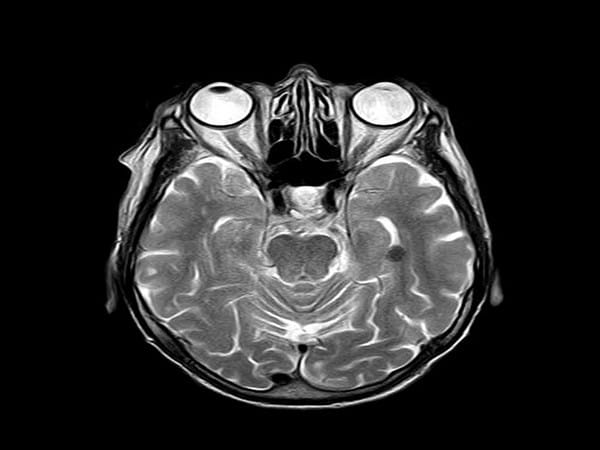

Human cortical organoids are derived from human induced pluripotent stem cells, which are usually derived themselves from skin cells. These brain organoids have recently emerged as promising models to study the development of the human brain, as well as a range of neurological conditions.

But until now, no research team had been able to demonstrate that human brain organoids implanted in the mouse cortex were able to share the same functional properties and react to stimuli in the same way. This is because the technologies used to record brain function are limited, and are generally unable to record activity that lasts just a few milliseconds.

By placing an array of these electrodes on top of the transplanted organoids, researchers were able to record neural activity electrically from both the implanted organoid and the surrounding host cortex in real time. Using two-photon imaging, they also observed that mouse blood vessels grew into the organoid providing necessary nutrients and oxygen to the implant.

Researchers applied a visual stimulus-an optical white light LED-to the mice with implanted organoids, while the mice were under two-photon microscopy. They observed electrical activity in the electrode channels above the organoids showing that the organoids were reacting to the stimulus in the same way as surrounding tissue. The electrical activity propagated from the area closest to the visual cortex in the implanted organoids area through functional connections. In addition, their low noise transparent graphene electrode technology enabled electrical recording of spiking activity from the organoid and the surrounding mouse cortex. Graphene recordings showed increases in the power of gamma oscillations and phase locking of spikes from organoids to slow oscillations from mouse visual cortex. These findings suggest that the organoids had established synaptic connections with surrounding cortex tissue three weeks after implantation, and received functional input from the mouse brain. Researchers continued these chronic multimodal experiments for eleven weeks and showed functional and morphological integration of implanted human brain organoids with the host mice cortex.